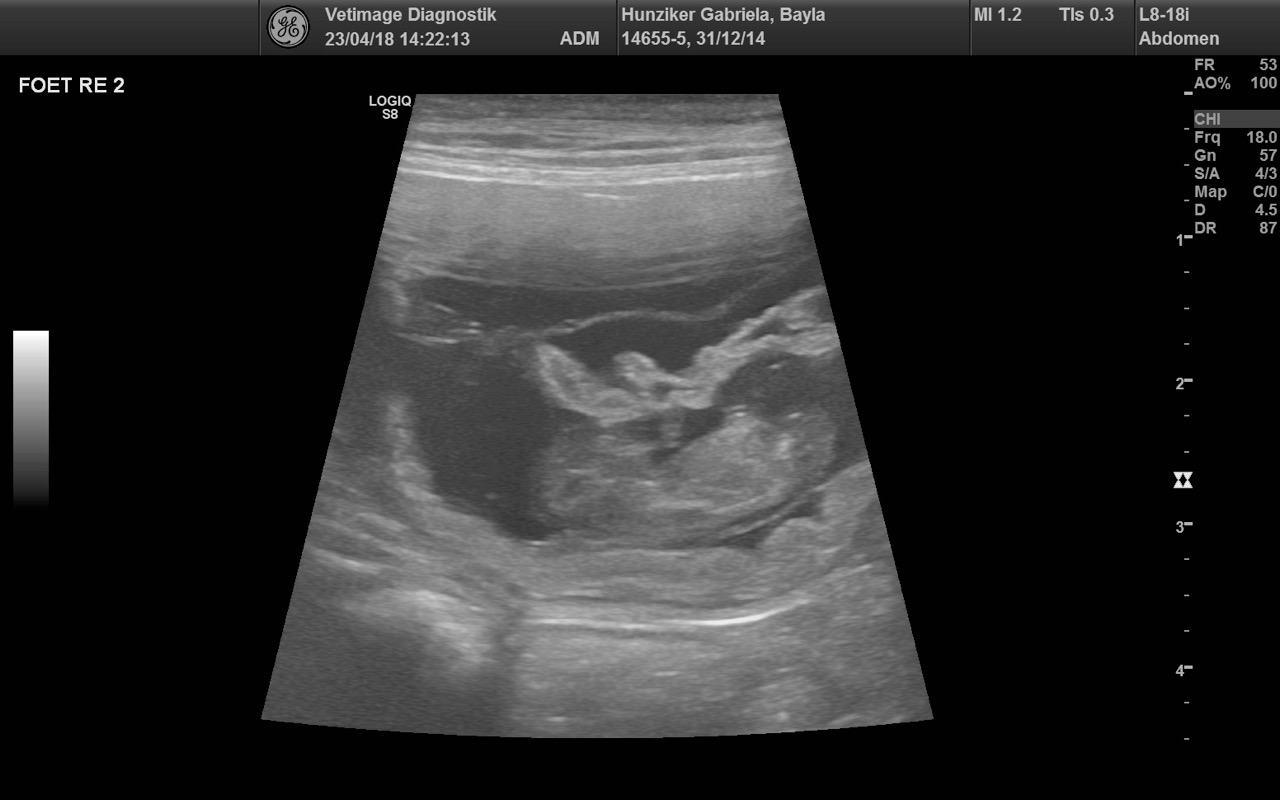

E-Wurf Ultraschall

Alle Anzeichen deuteten darauf hin... umso schöner ist es, dass wir beim Ultraschalluntersuch vom 23.4.2018 (VETIMAGE in Oberentfelden) die Bestätigung erhielten, dass Joya (Bayla Golden Harmony vom Rebhügel) trächtig ist.